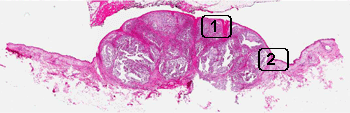

Hematoxylin & eosin

Area 1: Tumor involvement is limited to the dermis without infiltration into the epidermis. In fact, the tumor is separated from the dermis by a thin layer of fibrous tissue. On high magnification, the cells have hyperchromic nuclei, no prominent nucleoli, and only a small amount of cytoplasm. All of these are features of a so-called small blue cell tumor.

Area 2: This is taken at the junction between the tumor and the adjacent skin uninvolved by the carcinoma. There is a thick layer of bluish mucoid appearing material in the dermis of the uninvolved skin. These changes are what is termed solar elastosis and is indicative of sun damage. It is typically seen in sun exposed skin.